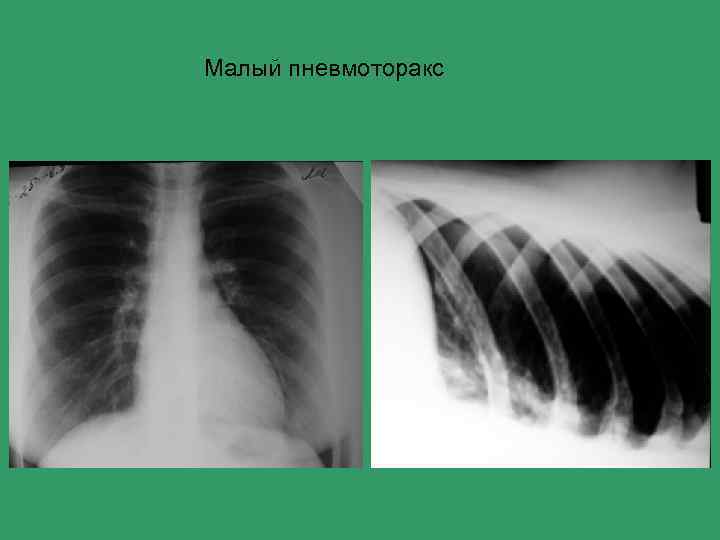

Алгоритм лучевого обследования при синдроме острой боли в грудной клетке внесердечной локализации Основные причины 1) 2) 3) 4) 5) 6) Острая пневмония Острый плеврит Спонтанный пневмоторакс ТЭЛА Острый живот (аппендицит, холецистит) Патология костной системы

Алгоритм лучевого обследования при синдроме острой боли в грудной клетке внесердечной локализации Уровень I НОРМА РЕНТГЕНОГРАФИЯ ГРУДНОЙ КЛЕТКИ ПАТ. КОСТИ? ПАТ. ПИЩЕВОДА? СРЕДОСТЕНИЕ? ПРИЦ. СНИМОК ЛИН. ТОМОГР. КОНТРАСТНОЕ ИССЛЕДОВАНИЕ ПНЕВМОТОРАКС? ПЛЕВРИТ? КОНТРЛАТЕРОГРАФИЯ УЗД ТЭЛА? ОТСРОЧЕННЫЙ СНИМОК Ур. II КТ СЦИНТИГРАФИЯ СКЕЛЕТА КТ АПГ

Малый пневмоторакс